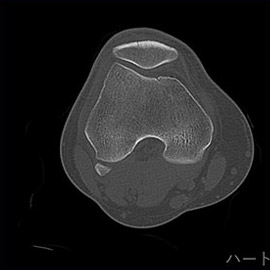

80列マルチスライスCT 検査 画像例

80列マルチスライスCTで撮影した画像

整形